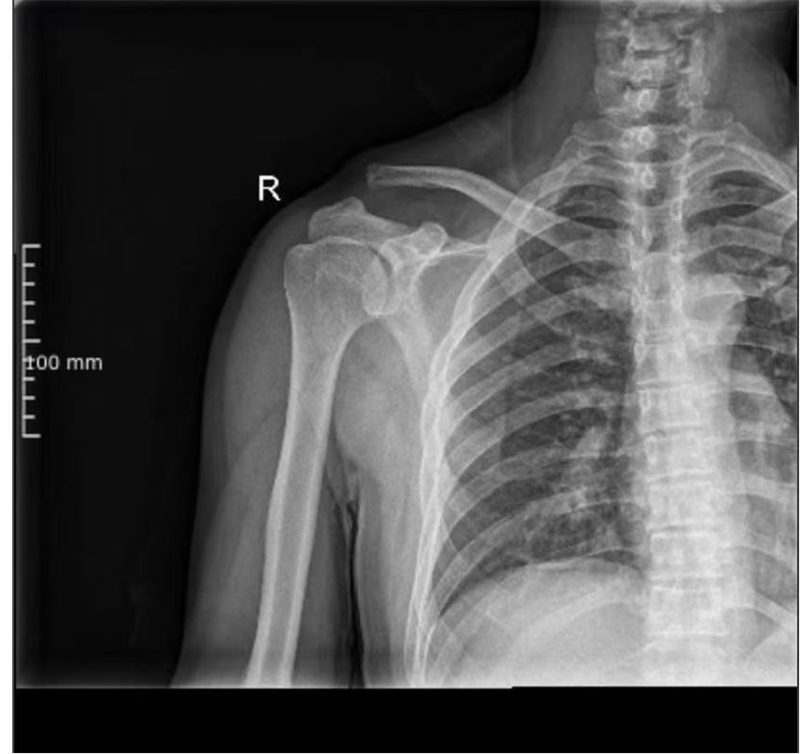

近期,寿光和信医院骨外科采取肩锁关节脱位切开复位袢钛板内固定术,一锚双袢固定,为肩锁关节脱位患者提供了一种全新的治疗选择。

肩锁关节是由肩峰内缘与锁骨外端组成的关节,其稳定由三部分装置维持:关节囊及其加厚部分形成的肩锁韧带、三角肌及斜方肌的腱性附着部分、喙锁韧带(斜方韧带与锥状韧带)。肩锁关节功能上属微动关节,与胸锁关节、肩胛骨胸壁连接共同构成肩胛带,主要有上下、前后、旋转三种基本运动形式。肩锁关节在参与肩锁关节大范围活动中有重要的协同作用,肩锁关节脱位是创伤骨科常见病,治疗不当可引起肩关节的疼痛及功能障碍。对RockwoodⅢ型肩锁关节脱位的治疗多数推荐手术治疗。

传统一般都是使用锁骨钩钢板治疗肩锁关节脱位,术中将尖钩紧贴肩峰下缘插入肩锁关节后方的肩峰下,3~4枚螺钉将钢板固定于锁骨,可获得良好的疗效。但钢板内固定术后最常见的并发症是肩部疼痛、肩峰下黏连导致肩关节术后活动受限及钩尖所致的肩峰切割,还需要二次手术取出钢板等,给患者带来很多不便。